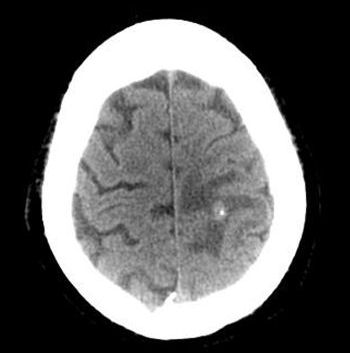

This patient was a 47 year old male who had a two-months history of numbness on his right side. MRI of the brain with and without contrast revealed multiple small enhancing lesions consistent with probable metastatic disease. The largest lesion was in the left parietal area (Figure 1 [Fig. 1]). Chest, abdomen and pelvis CT showed a 2.5×1.8 cm lesion in his left kidney (Figure 2 [Fig. 2]). The patient had no significant medical history other than an operation for a perforated ulcer 15 years ago. The patient admitted to smoking a pack and a half of cigarettes a day and drinking alcohol daily. There were no significant findings on physical exam. It was decided that the definitive treatment would depend on pathology and therefore surgery was undertaken. Pathology showed tubular structure (Figure 3A, Figure 3B, Figure 3C[Fig. 3]) with immunoreactivity to cytokeratin AE1/AE3 (Figure 3D [Fig. 3]) but negative for cytokeratin 7 and 20. The histologic features and immunoprofile was compatible with renal cell carcinoma. The patient then had 14 radiation seances to the brain; after that he was put on the new drug, sorafenib (approved by the U.S. Food and Drug Administration in December 2005). The tumor kidney was removed 11 months after metastasis resection. On his followup visit three years later the patient was neurologically intact. He was on phenytoin and sorafenib. The last MRI, 4 years after the initial surgery, looks stable without residual or recurrent tumor.